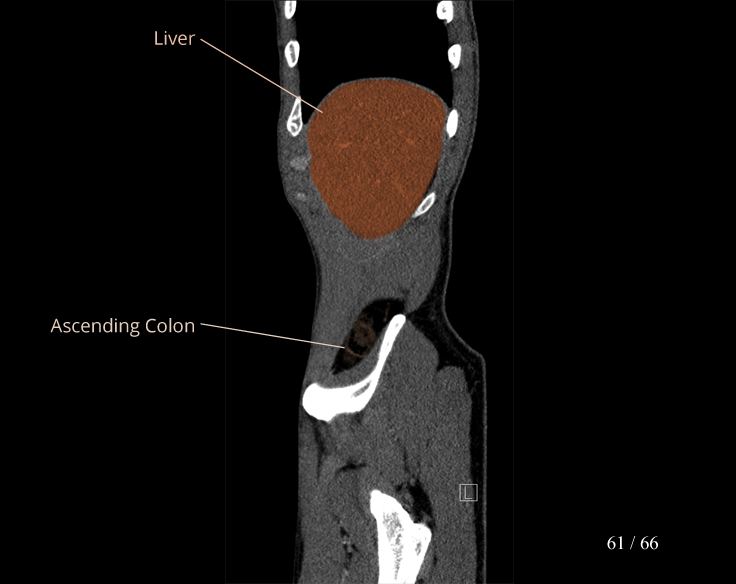

Body

Covers abdominal CT anatomy.